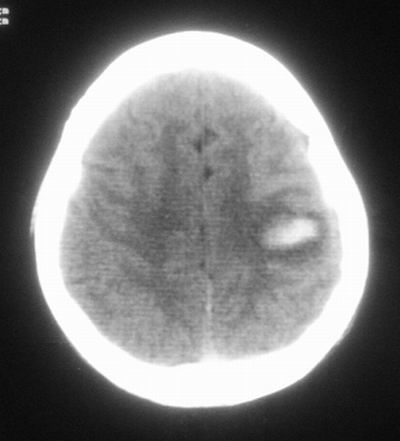

患者,男,30岁,右侧面部麻木,右上肢活动受限27小时。pe:神清、呼吸平稳,口角左歪,右上肢活动受限,右手掌握力消失,右侧躯体痛觉减退。

第一次颅脑ct扫描:左侧额顶叶血肿。